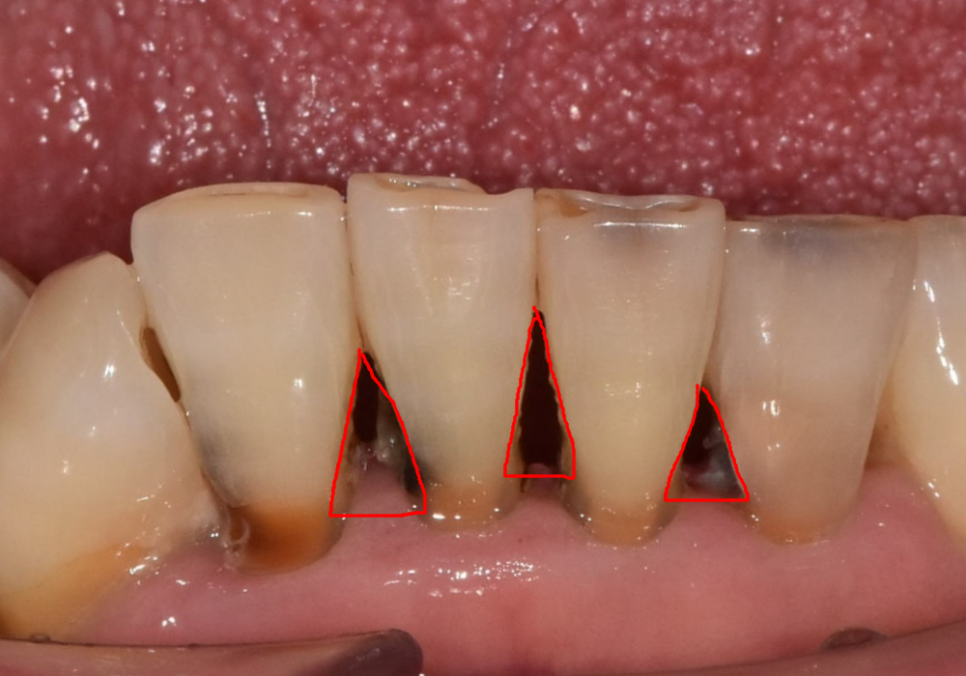

나이가 들수록 치아 사이가 벌어지는 건

자연스러운 노화 현상 중 하나예요.

잇몸이 조금씩 내려앉으면서

치아 사이에 빈 공간인

블랙 트라이앵글이 생기기 때문이죠.

블랙 트라이앵글이라는 말이

조금 생소하시죠?

쉽게 말해 치아와 치아 사이,

그리고 잇몸 경계 부분에 생기는

삼각형 모양의 작은 빈 공간을 뜻해요.

원래는 분홍색 잇몸이

그 자리를 꽉 채우고 있어야 하지만,

나이가 들거나 잇몸 질환이 생기면

잇몸이 아래로 내려가게 됩니다.

이 공간은 음식물이 머물기

아주 좋은 장소가 됩니다.

틈새로 음식물이 반복해서 끼면

치아 사이 충치가 발생하기 쉽고,

이는 치아 내부를 까맣게 변색시키는

주범이 된답니다.